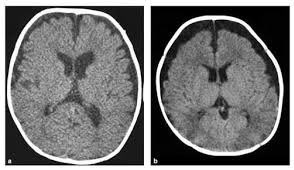

عادةً مايتضمن التشخيص اختباراً بدنياً يتبعه اختباراتٍ معينةٍ،ويظهر ضمور الدماغ في عمليات مسح تصوير الدماغ منها:

*الأشعةالمقطعية(CT)مثل صور الأشعةالسينية من زوايا مختلفةٍ لإنشاء صورٍ مفصلةٍ للدماغ